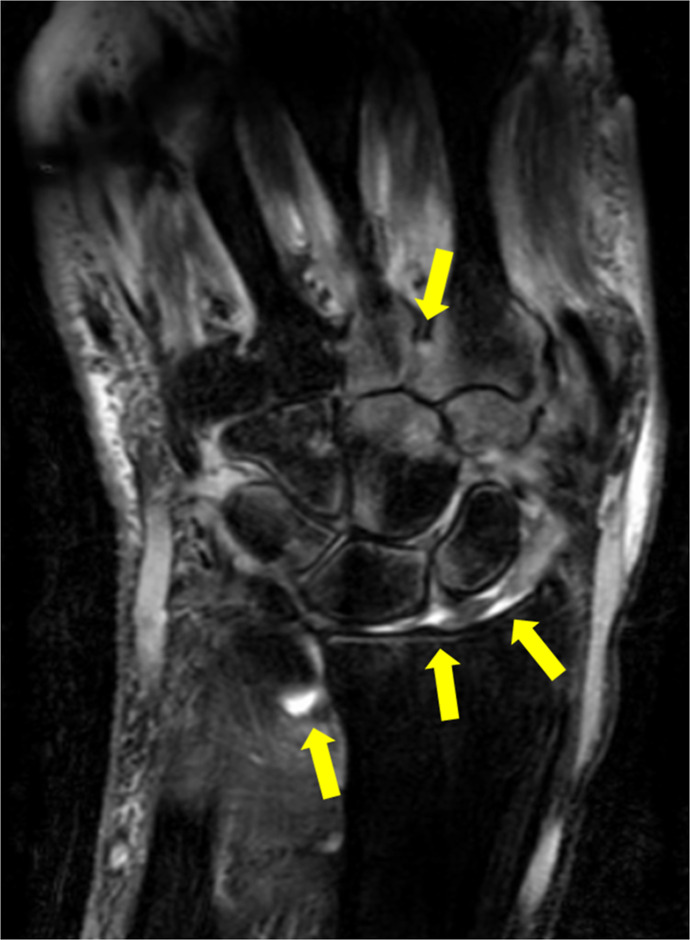

Introduction: Psoriasis is a chronic systemic inflammatory disorder resulting from complex interactions between genetic and environmental factors. In addition to cutaneous manifestations, psoriasis is associated with psoriatic arthritis (PsA). Among the recognized mechanisms of disease exacerbation, the Köbner phenomenon (KP) plays a crucial role. KP refers to the appearance of new psoriatic lesions on previously healthy skin following trauma. A deeper variant of this phenomenon, the deep Köbner phenomenon (DKP), involves severe trauma triggering systemic inflammation, including the onset of PsA. Trauma-induced DKP represents unique disease mechanisms, linking external mechanical stress to immune-mediated joint pathology.

Case presentation: We present a case of a 60-year-old male with psoriasis, who initially responded well to ixekizumab, an IL-17A inhibitor but subsequently developed PsA following a wrist injury. The PsA exacerbation was attributed to increased mechanical stress from daily activities and rehabilitation efforts. Adjustments were made to rehabilitation intensity and joint movement restrictions, leading to gradual symptom improvement over 3 months without intensifying biological therapy.

Conclusion: This case highlights the pathophysiological relationship between trauma, DKP, and PsA. The rapid onset of PsA following trauma suggests that inflammatory mediators and neuropeptides triggered by DKP play significant roles. Given that rehabilitation plays crucial roles in recovery but may also exacerbate symptoms if improperly managed, tailored rehabilitation strategies are essential in managing trauma-induced PsA. This case also underscores the importance of comprehensive management, including biological therapy and personalized rehabilitation approaches. Further studies are needed to optimize inflammation control and joint function in patients experiencing post-trauma PsA.